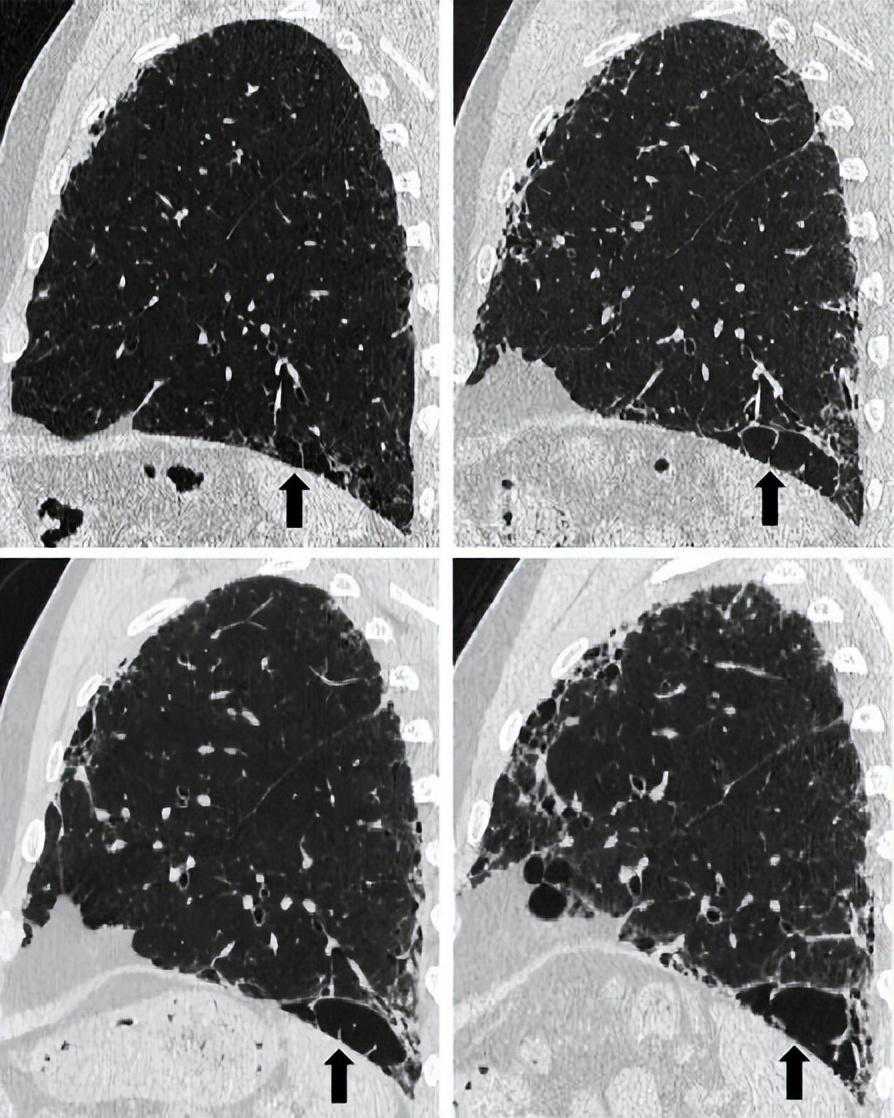

图3:HRCT显示典型的肺纤维化和肺气肿(间隔旁肺气肿模式)的典型分布。67岁男性,诊断为特发性肺纤维化,广泛孤立的间隔旁和小叶中央肺气肿出现在上部区域。尽管小叶中央型肺气肿多孤立于中段,但间隔旁肺气肿越来越混杂,类似于左肺中的蜂窝状囊肿。在左下叶内,间隔旁的肺气肿类似蜂窝囊肿,与形状不规则的小叶中心型肺气肿相邻。

图4:HRCT显示混合性破坏性肺气肿恶化(合并肺纤维化和肺气肿,混合型)。一位66岁男性特发性肺纤维化患者的(A和B)肺上区和(C和D)肺下区,相隔2年(A和C:基线;B和D:随访)的轴位图像中,随着时间的推移,右上叶的孤立性肺气肿与纤维化混合在一起。在左下叶,中央位置的肺气肿变得分离(牵引性肺气肿),并随着周围纤维化的进展而扩大。